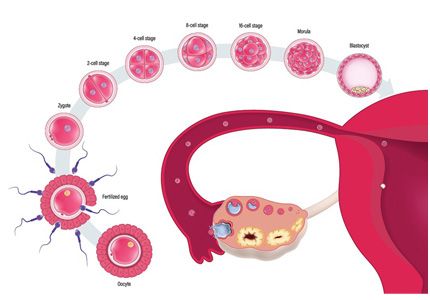

השבוע הראשון להריון

מבט מקרוב על הרגע הקסום שבו מתחילים חיים חדשים: מרגע המפגש בין הזרע לביצית ועד להשתרשות ברחם. נבין את התהליכים הביולוגיים המורכבים והקריטיים שמתרחשים בימים הראשונים שלאחר ההפריה.